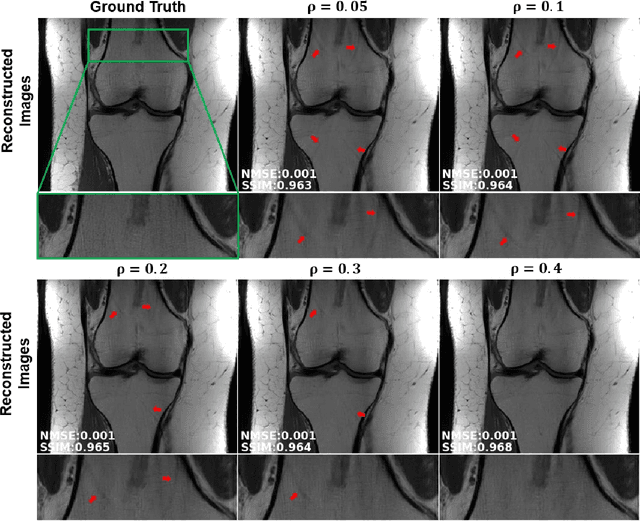

Abstract:Physics-guided deep learning (PG-DL) via algorithm unrolling has received significant interest for improved image reconstruction, including MRI applications. These methods unroll an iterative optimization algorithm into a series of regularizer and data consistency units. The unrolled networks are typically trained end-to-end using a supervised approach. Current supervised PG-DL approaches use all of the available sub-sampled measurements in their data consistency units. Thus, the network learns to fit the rest of the measurements. In this study, we propose to improve the performance and robustness of supervised training by utilizing randomness by retrospectively selecting only a subset of all the available measurements for data consistency units. The process is repeated multiple times using different random masks during training for further enhancement. Results on knee MRI show that the proposed multi-mask supervised PG-DL enhances reconstruction performance compared to conventional supervised PG-DL approaches.